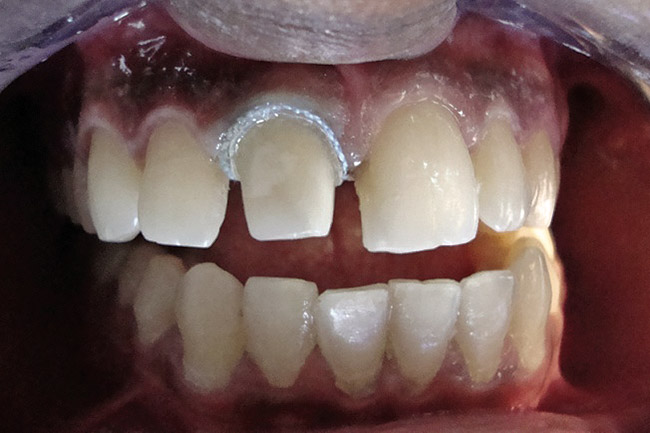

Figure 2  Caries extending cervically on upper right incisors.

Figure 2

Figure 3  Placement of rubber dam with application of cervical clamp on central incisor for extra retraction.

Figure 3